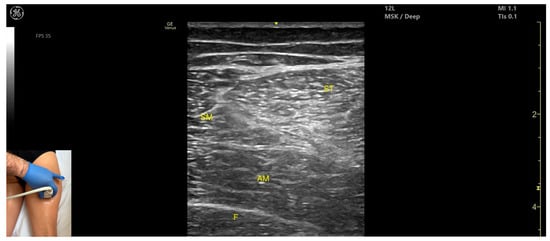

3.9. Semimembranosus (SM)

3.9.1. Overview

3.9.2. Ultrasound Identification

3.9.3. Key Ultrasound Landmarks

- Muscle position: It is a superficial muscle mass at this level. It is the first muscle seen from medial to lateral on the posterior surface of the thigh. Deep and medial to it lies the adductor magnus, while laterally to it lie the semitendinosus and biceps femoris muscles. The sciatic nerve is located deep and lateral to the SM and semitendinosus and deep to the biceps femoris. The popliteal vascular bundle is visualized deep to the muscle in the distal third of the posterior thigh.

- External fascia: It has a pronounced fascia that separates it from the subcutaneous tissue, semitendinosus, and adductor magnus, aiding in safe botulinum toxin injection.

- Dynamic evaluation: During dynamic evaluation, scanning proximally toward the hip joint, the SM decreases in thickness, while the semitendinosus increases; the sciatic nerve remains lateral and deep to the semitendinosus. Contraction is visible during hip extension, knee flexion, and the internal rotation of the leg.